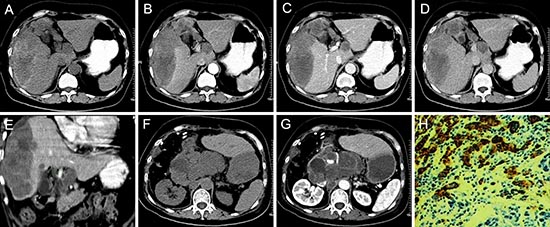

Figure 5: pPNET in a 66-year-old woman. Precontrast CT images showed an irregular heterogeneous low-density mass with hemorrhage and ill-defined margins in the right lobe of the liver (A). The enhanced CT scan showed the mass had slight ring enhancement (B-D). Coronal reconstruction of the enhanced CT images showed the mass invaded the hepatic portal vein (E). The patient had recurrence and retroperitoneal lymph node metastases one month after surgery (F and G). The poorly differentiated small round tumor cells were CD99 positive (H × 100).